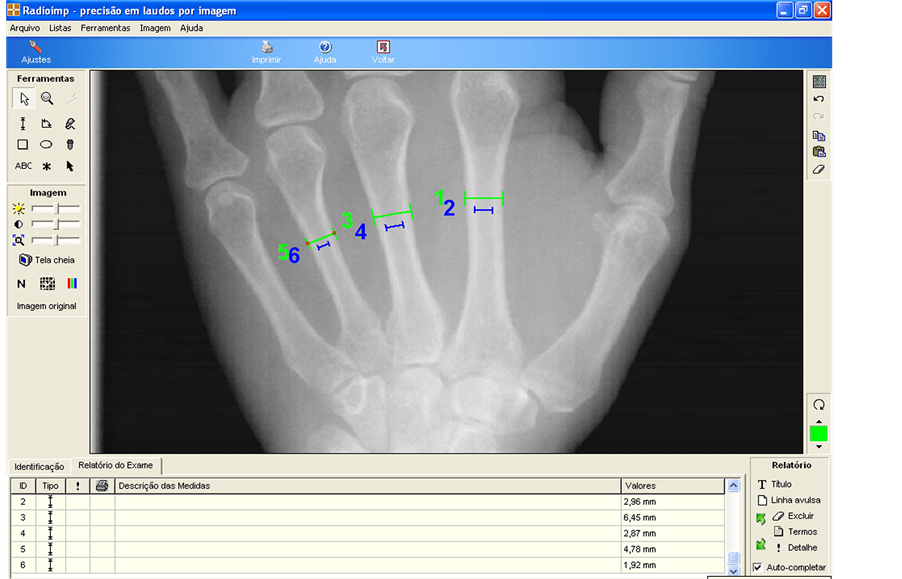

In carpal radiographs were performed measurements of the internal and external cortical thickness in 2nd, 3rd and 4th metacarpals. These measurements resulted in the Metacarpal Index (MCI) or Nordin Index (Figure 4).

Figure 4. Measurement of Metacarpal Index (MCI) using the software program Radioimp (Radio Memory, Belo Horizonte, Brazil).